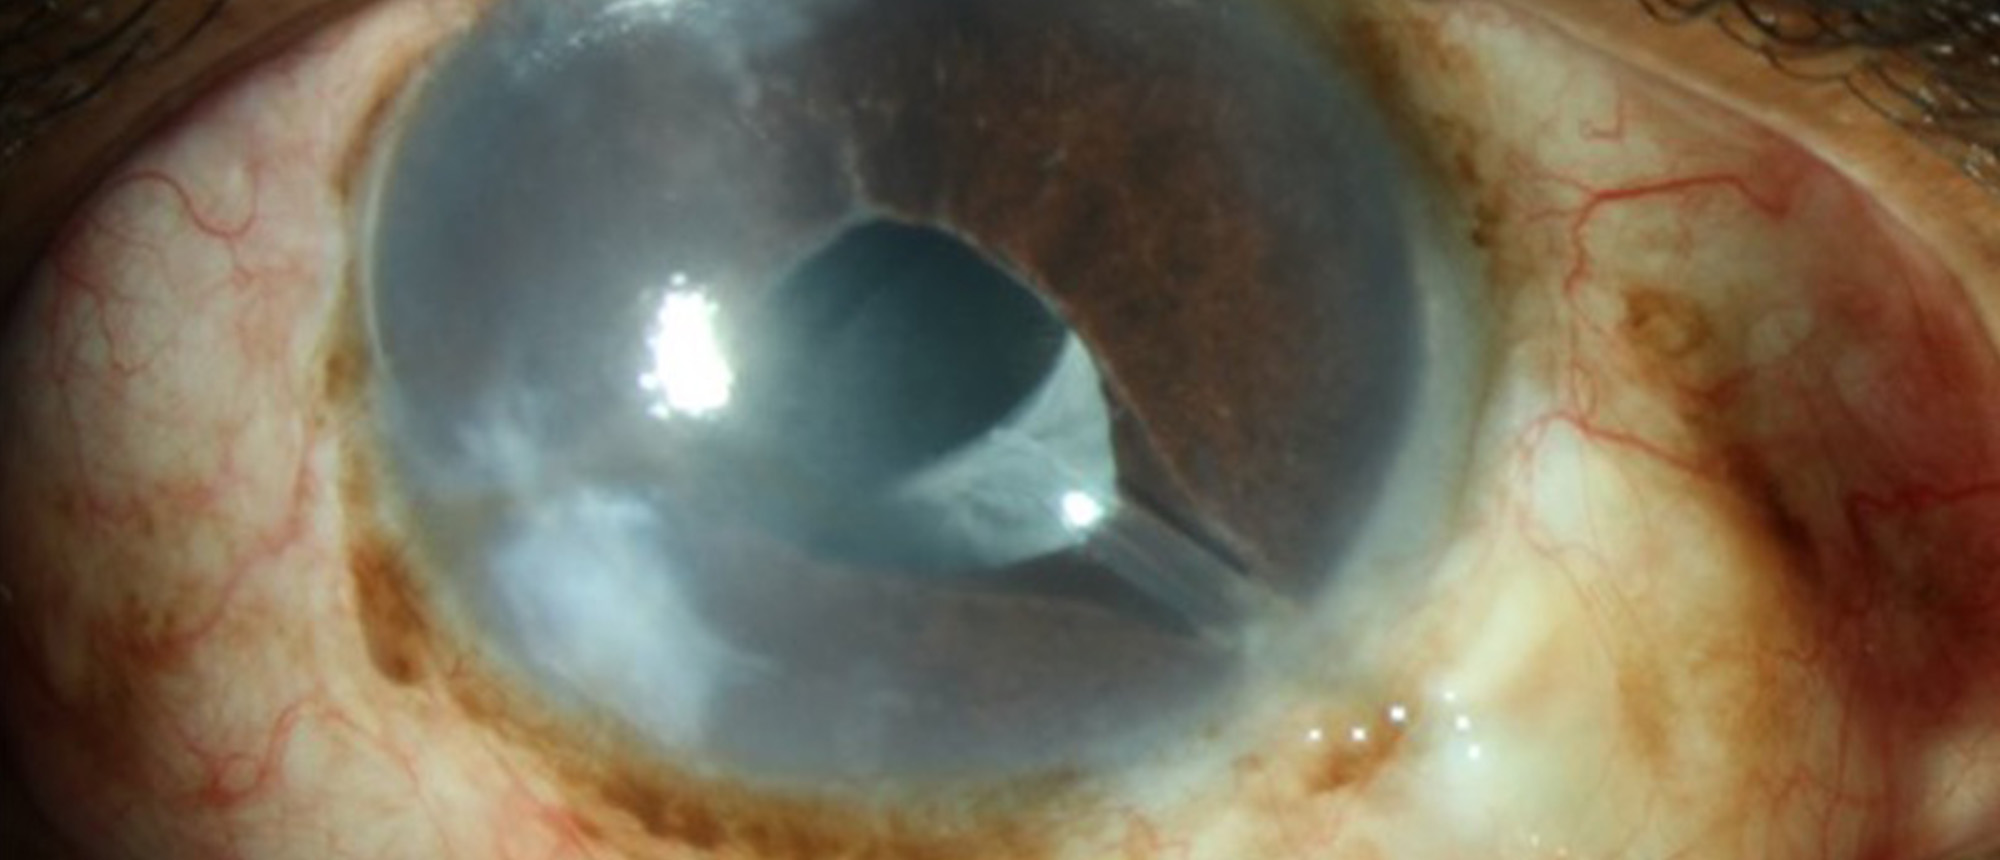

Marfan Syndrome with Ectopia Lentis A young child presented to the ophthalmology clinic with blurry vision. Slit lamp examination was notable for superotemporally subluxed lenses in both eyes, along with a tall slender body frame. Due to these findings, the patient was referred to a geneticist and …